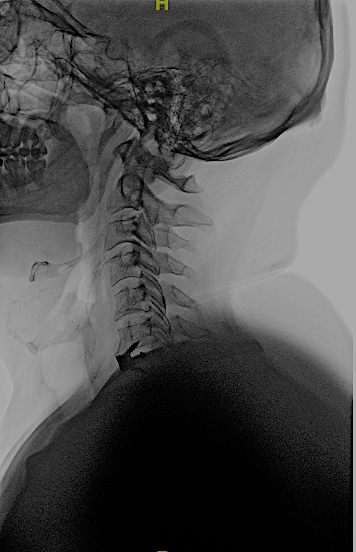

CASO CLÍNICO 2: HERNIA DISCAL C7-TH1 ASOCIADA A ESTENOSIS DE CANAL

Paciente de 46 años que consulta por clínica de mielopatía cervical de evolución progresiva en los últimos dos meses. Tuvo una braquialgia derecha 4 meses antes que mejoró con tratamiento conservador.

Este caso me parece interesante porque hubiese podido ser tratado por vía posterior al ser una hernia lateral, sin embargo, no se trataba de una afectación segmentaria aislada sino que en la misma RM podía apreciarse estenosis de canal en C6-C7 con compresión medular a dicho nivel. No hay que olvidar que el motivo de la consulta fue la instauración de una mielopatía cervical progresiva (inestabilidad, urgencia miccional e hiperreflexia) pues la braquialgia derecha estaba en proceso de remisión.

Por las razones expuestas, a pesar de un thoracic inlet angle bastante alto, opté por realizar un abordaje anterior con descompresión + artrodesis IS con cajas atornilladas C7-Th1.

La evolución clínica fue favorable. En la RX control lateral apenas podemos visualizar la caja inferior sin embargo, por la ausencia de dolor, por la falta de edema en STIR en cuerpos vertebrales C7-Th1 y por la resolución de la clínica neurológica no considero imprescindible por ahora, someter al paciente a un TC cervical (gran radiación en paciente joven).